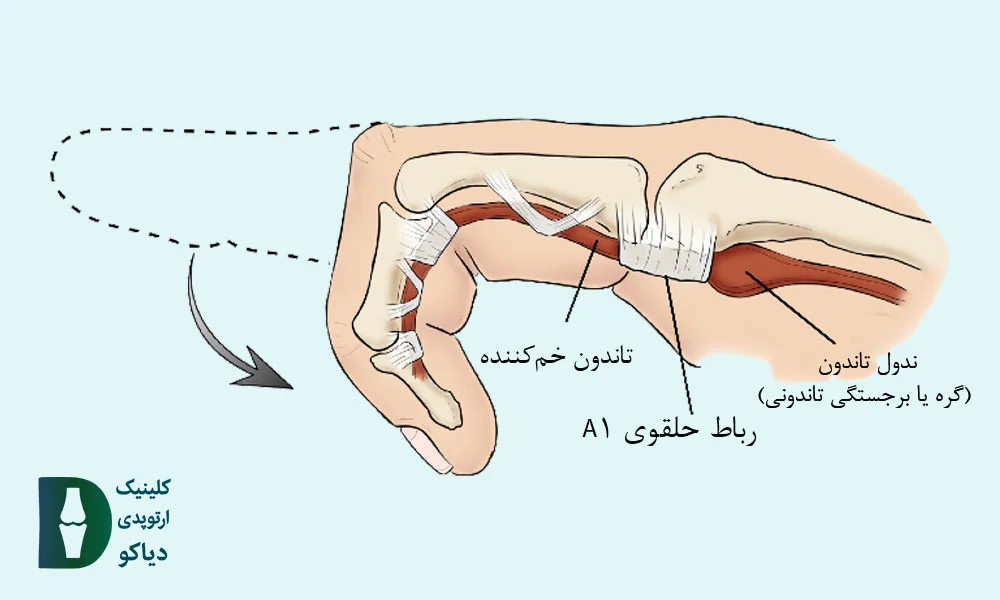

در بزرگسالان، انگشت ماشهای اغلب بهدلیل التهاب و ضخیمشدن غلاف تاندون خمکننده (بهویژه در ناحیهی A1 pulley ) ایجاد میشود؛ وضعیتی که باعث گیر کردن تاندون در مسیر حرکتش شده و هنگام باز یا بسته کردن انگشت، احساس قفلشدگی، صدای تق یا درد بهوجود میآورد.

در بیماران با گرید 2 و 3a، که انگشت هنگام حرکت دچار قفلشدگی میشود ولی هنوز قابلیت صافشدن دارد (چه بهصورت فعال یا با کمک دست دیگر)، درمانهای غیرجراحی میتوانند بسیار مؤثر باشند و از پیشرفت بیماری یا نیاز به جراحی جلوگیری کنند. در این مراحل، هدف درمان، کاهش التهاب غلاف تاندون، بهبود حرکت تاندون درون رباط حلقوی A1 و پیشگیری از چسبندگیهای بیشتر است.

تزریق کورتون معمولاً در محل غلاف تاندون A1 در پایه انگشت، نزدیک سر استخوان کفدستی انجام میشود.

تزریق داروی کورتون (معمولاً تریامسینولون یا دگزامتازون) در ناحیهی غلاف تاندون A1، درست بالای استخوان کفدستی (متاکارپال)، میتواند التهاب را کاهش دهد و حرکت تاندون خمکننده را تسهیل کند. این درمان در بیماران با انگشت ماشهای گرید 2 و 3a معمولاً بسیار مؤثر است. اغلب بیماران طی ۳ تا ۷ روز بهبود قابلتوجهی در درد و گیرکردن انگشت تجربه میکنند. در اکثر موارد، یک نوبت تزریق کافی است؛ اما در موارد مقاوم، ممکن است نیاز به تزریق دوم نیز وجود داشته باشد.

عمل جراحی معمولاً بهصورت سرپایی و با بیحسی موضعی انجام میشود. جراح با ایجاد یک برش کوچک در کف دست، رباط حلقوی A1 را که تاندون را تحت فشار قرار داده، برش میدهد تا مسیر حرکت تاندون باز و بدون اصطکاک شود. این فرایند معمولاً کمتر از ۲۰ دقیقه زمان میبرد و نیاز به بستریشدن در بیمارستان ندارد.